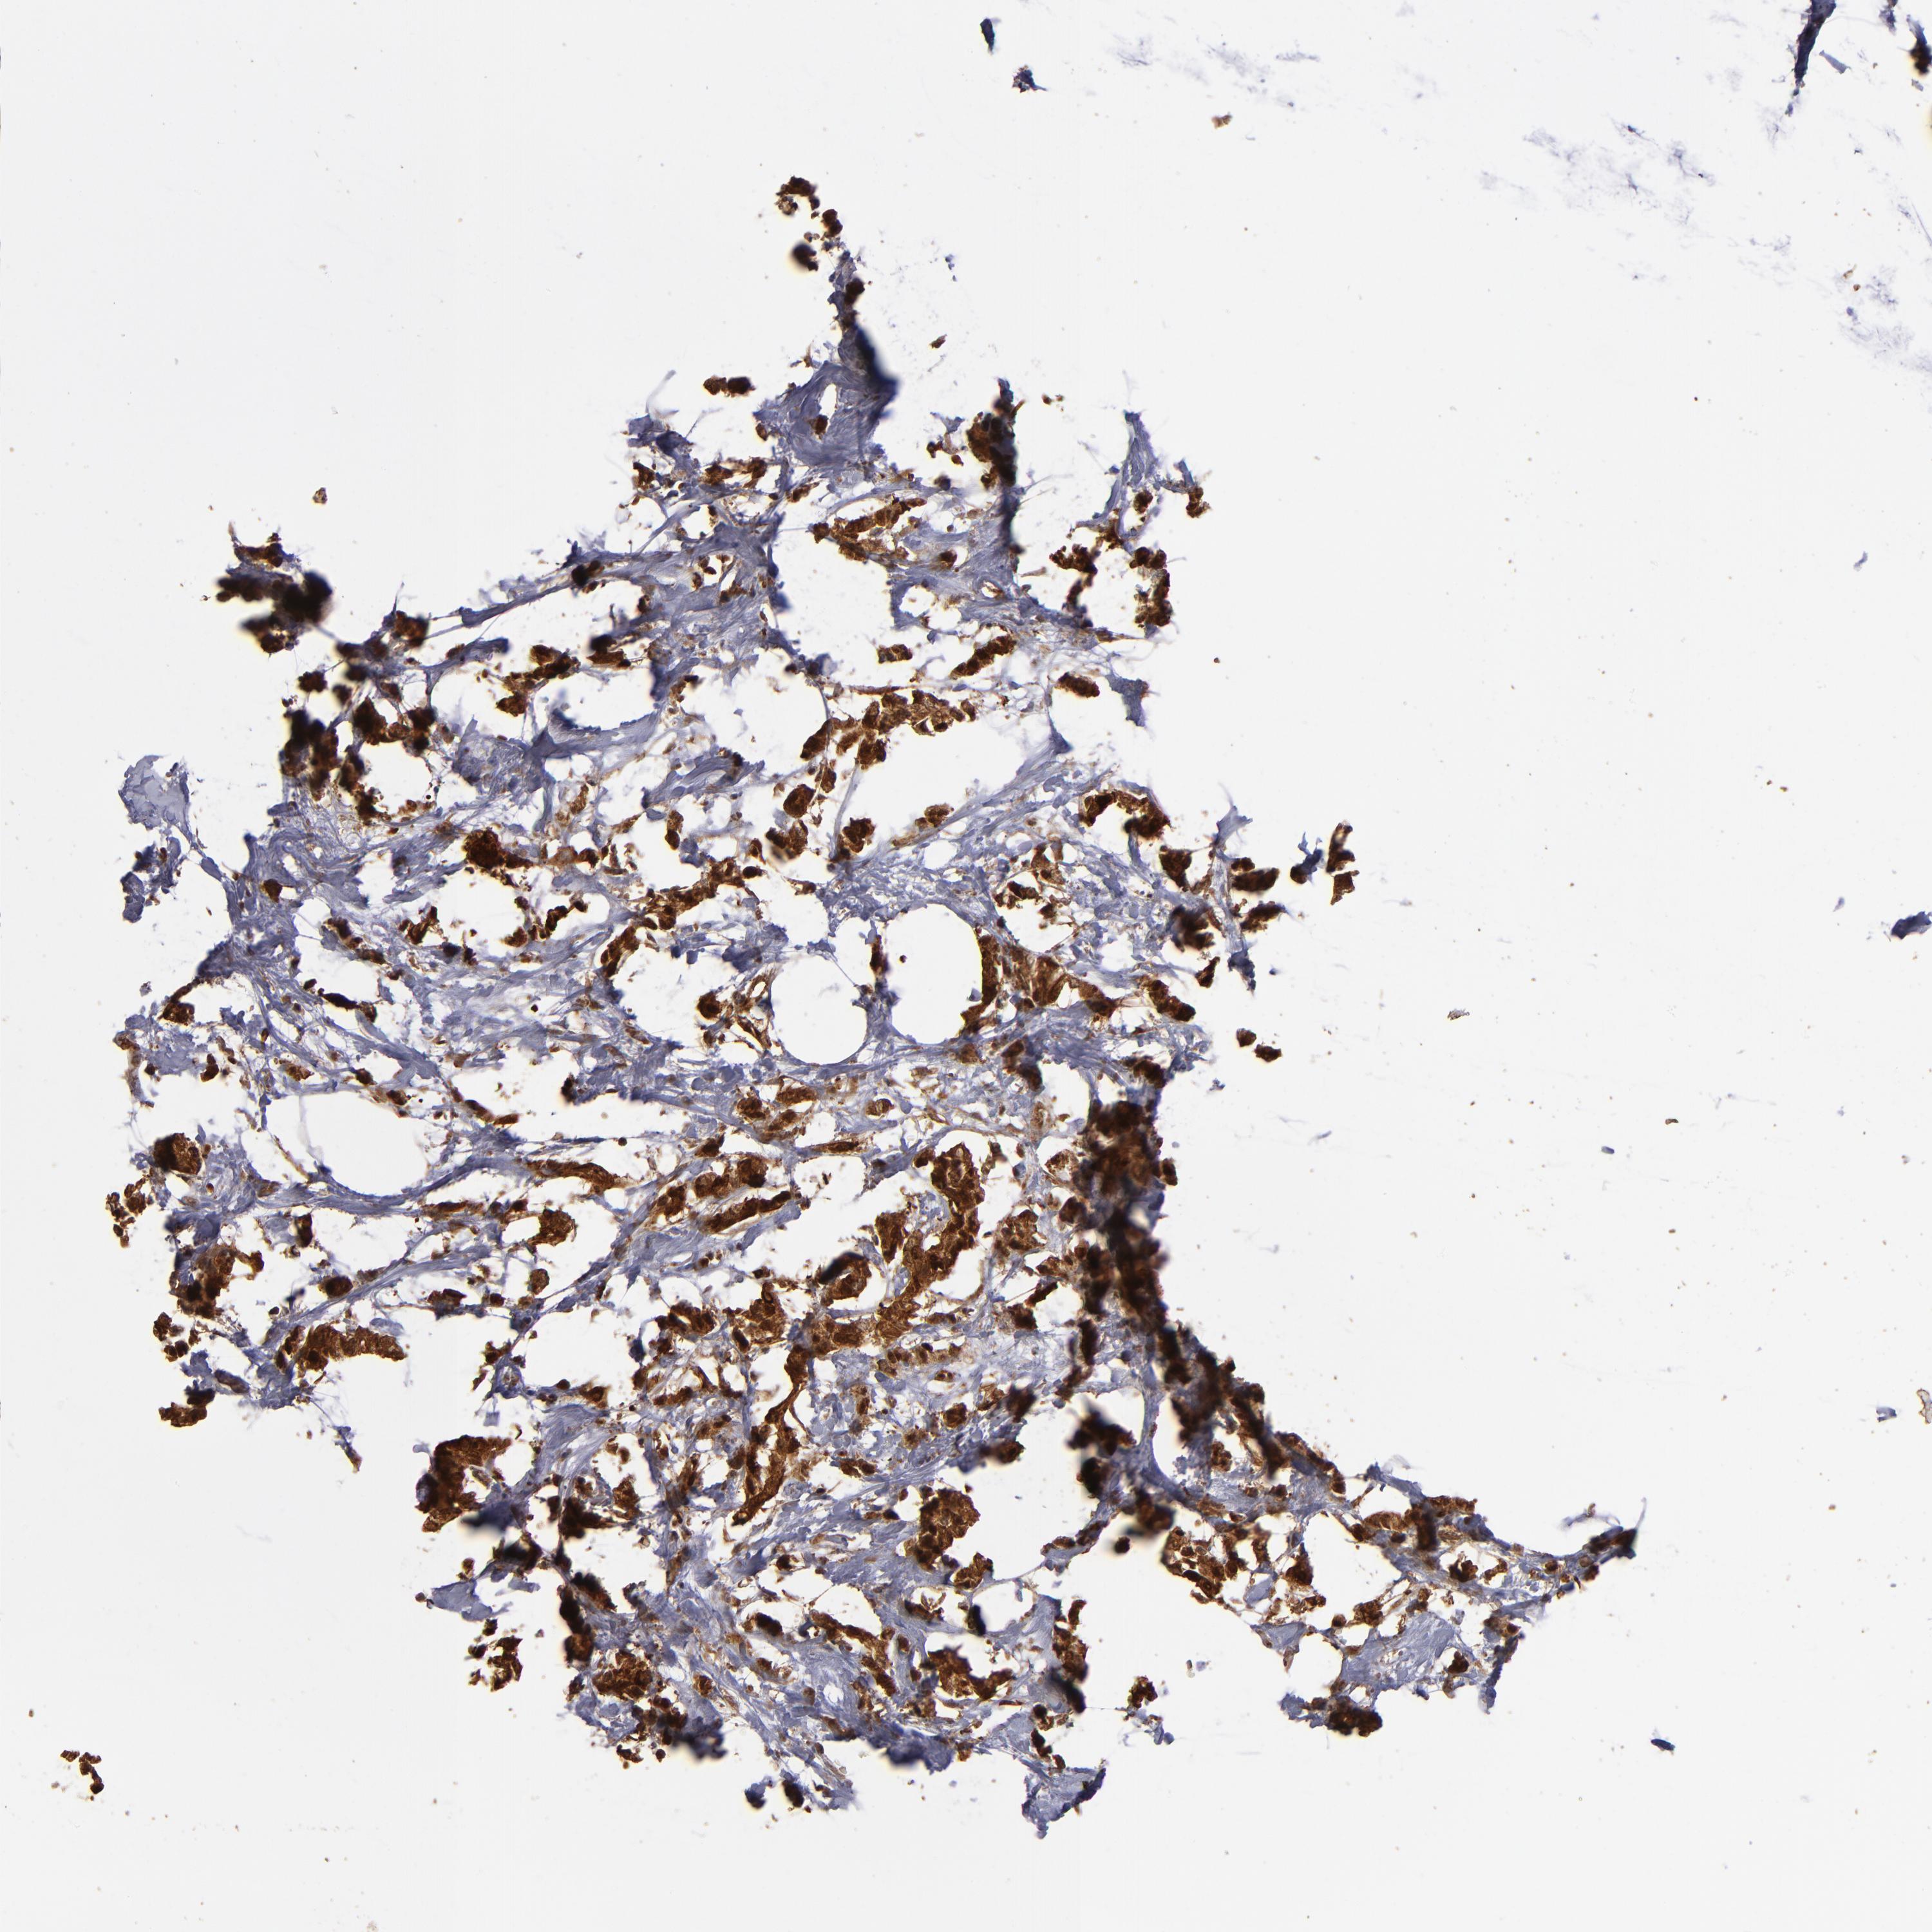

BRCA TCGA BRCA VALIDATION PROTEIN EXPRESSION

ANTIBODIES

AND

VALIDATION